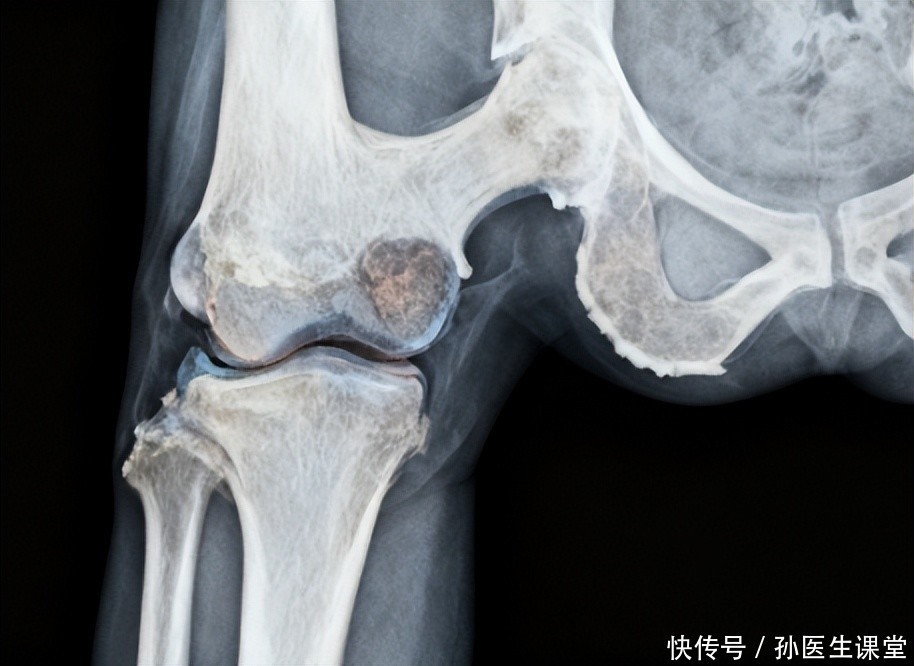

骨关节炎发出的信号其实很 “温和”,不会突然让人痛到无法站立,却会悄悄影响生活。比如走一段路后膝盖发沉、发酸,休息几分钟又能缓解,很多人会把这当成 “累着了”;还有人发现膝盖在阴雨天会隐隐作痛,以为是 “风湿”,随便贴张膏药就应付过去。更常见的是晨起时膝盖僵硬,得活动十分钟才能灵活,这些细微的变化,其实都是膝盖在提醒我们 “该关注我了”。

有位邻居阿姨,之前每天都去公园跳广场舞,后来觉得膝盖疼,就改成了慢走,可疼痛却越来越明显,甚至上下楼梯都得扶着扶手。去检查后才知道是骨关节炎,她后悔地说:“早知道当初疼的时候就来看看,还以为多走走路就能好,没想到反而加重了。” 其实很多人都有类似的误区,觉得膝盖疼是 “缺乏锻炼”,反而用错误的方式加重了膝盖负担。